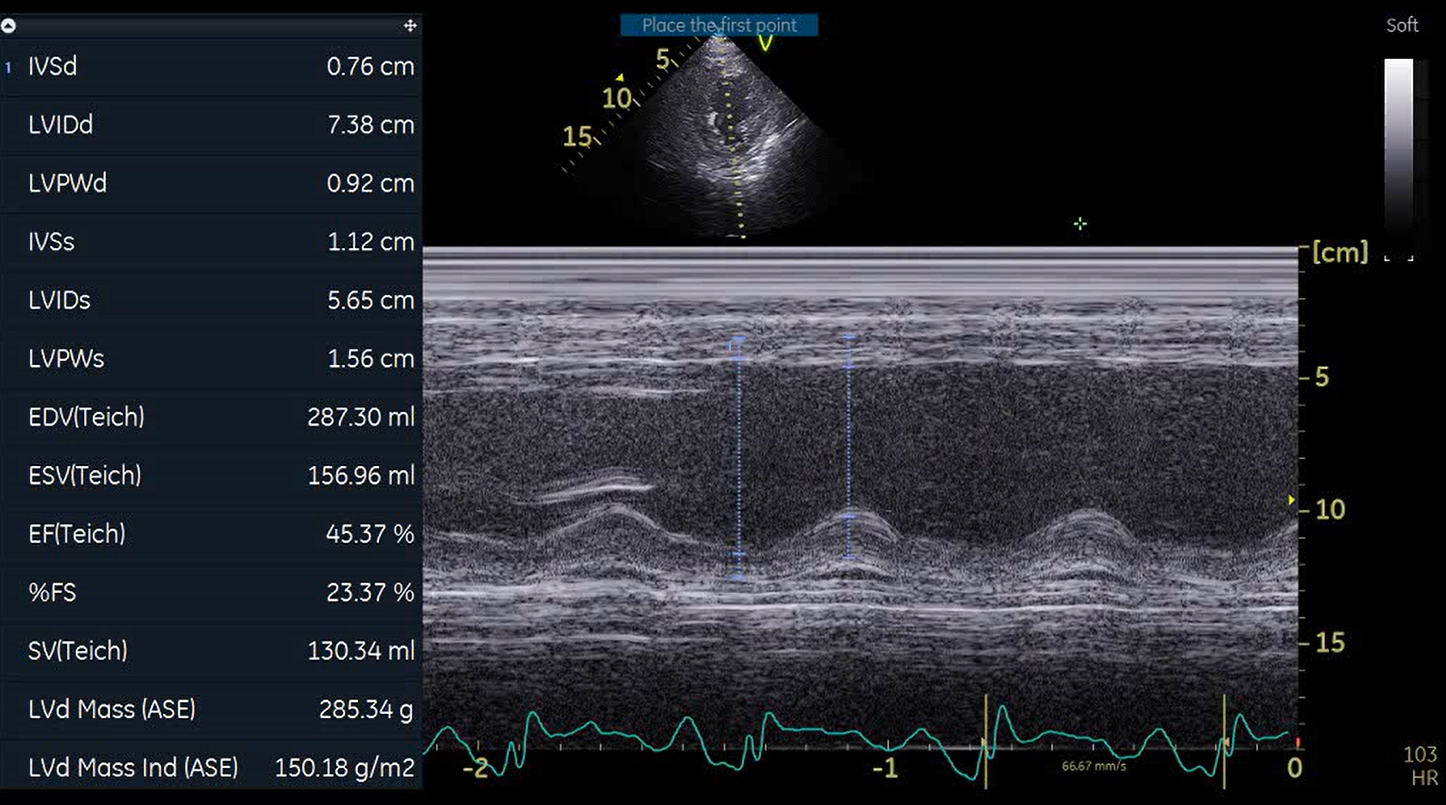

A covered stent was deployed in the distal LAD in an attempt to seal the coronary perforation; however, angiography showed that the Type III perforation persisted despite the intervention. Additional balloon inflation within the stent was performed, but the leakage could not be completely sealed. The patient remained hemodynamically stable without signs of cardiac tamponade or pericardial effusion. The following day, repeat coronary angiography was conducted to reassess the condition, which confirmed persistent contrast extravasation from the LAD into the left ventricular cavity, indicating the formation of a coronary–ventricular fistula. Given the hemodynamic significance and the risk of progressive left ventricular dysfunction due to continuous shunting, a multidisciplinary decision was made to proceed with surgical correction. The patient subsequently underwent successful LAD–LV fistula patch repair combined with. Surgical repair remains the definitive management for such cases, and early recognition with timely intervention is crucial to restore cardiac function and prevent irreversible myocardial damage.

The patient underwent successful surgical patch closure of the LAD–LV fistula along with ventricular reconstruction to restore myocardial integrity. The postoperative recovery was smooth and uneventful, with stable hemodynamics throughout hospitalization. Follow-up echocardiography demonstrated significant improvement in LVEF to 53%, and she remained asymptomatic during subsequent outpatient follow-up